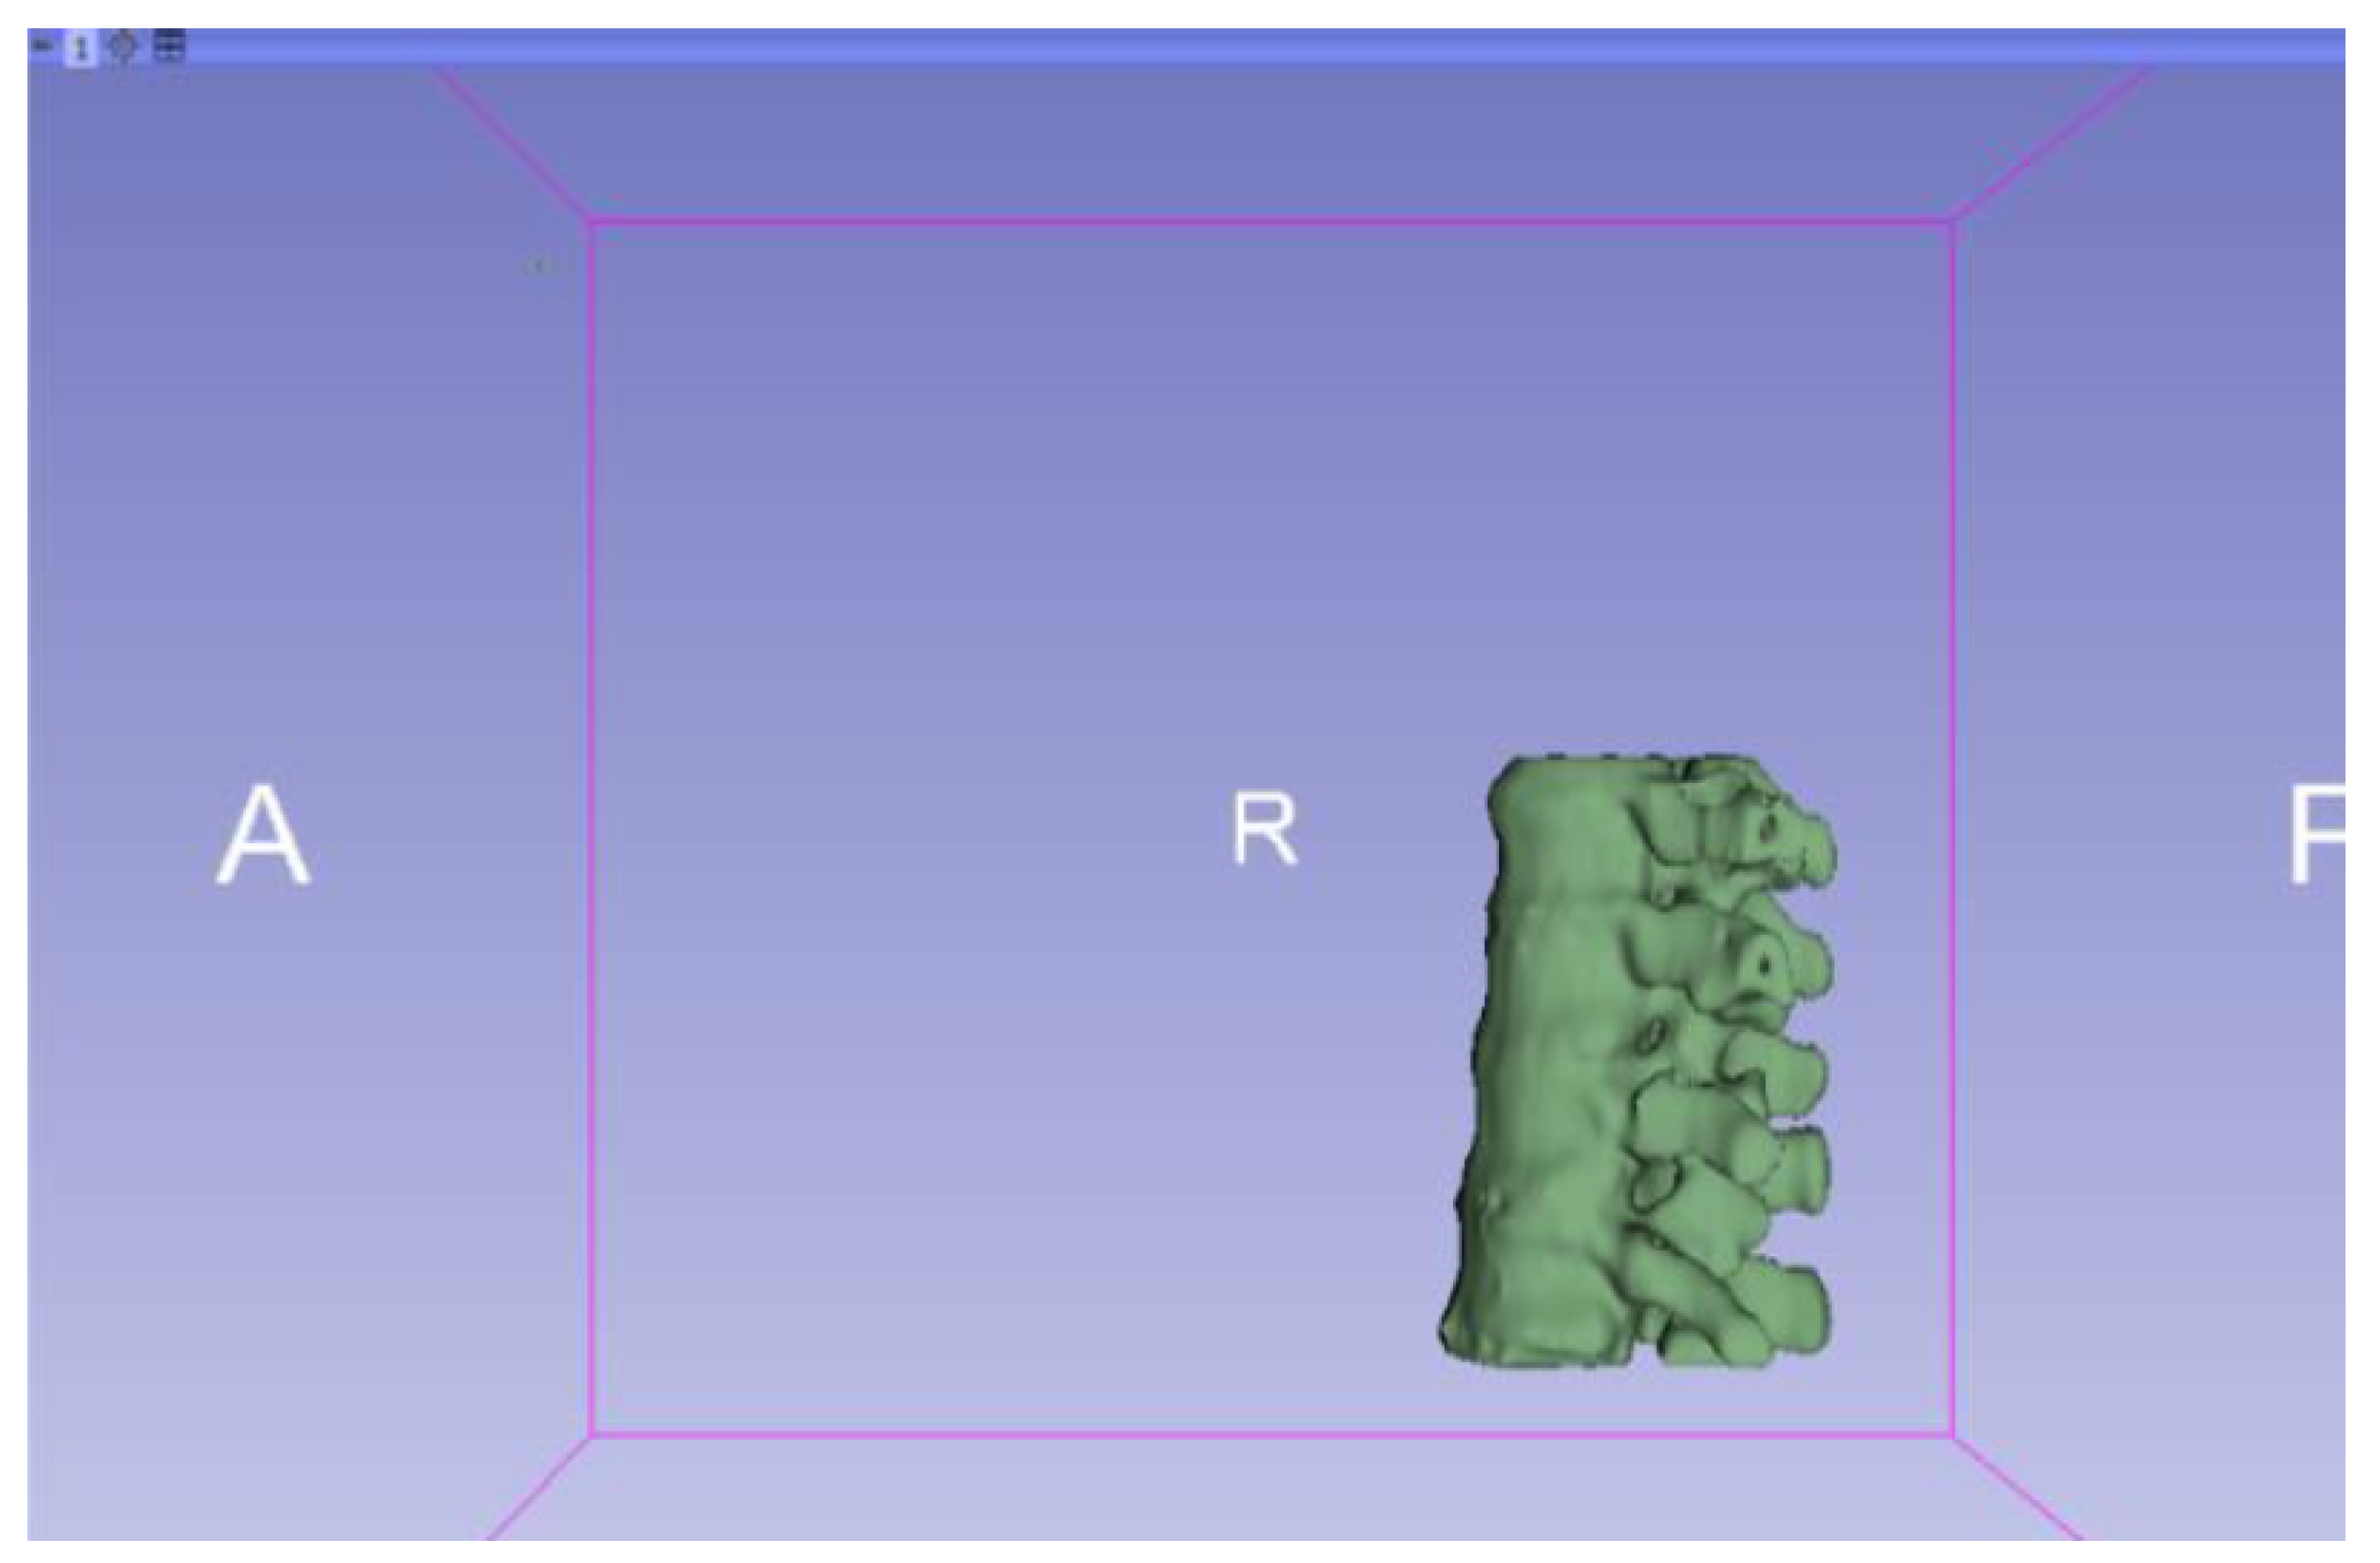

3.1.1. DICOM-to-STL File

| Vertebrae | [150, 300] | Median | 0.8 | 0.18 | 25 |